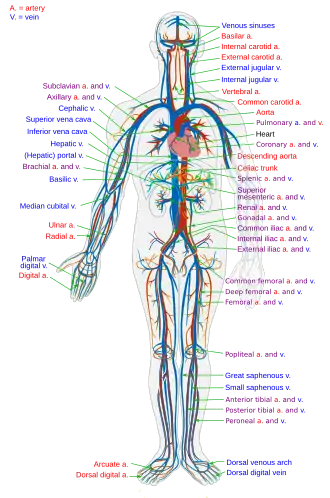

Selected image –

General images –

Anatomy - Biological engineering